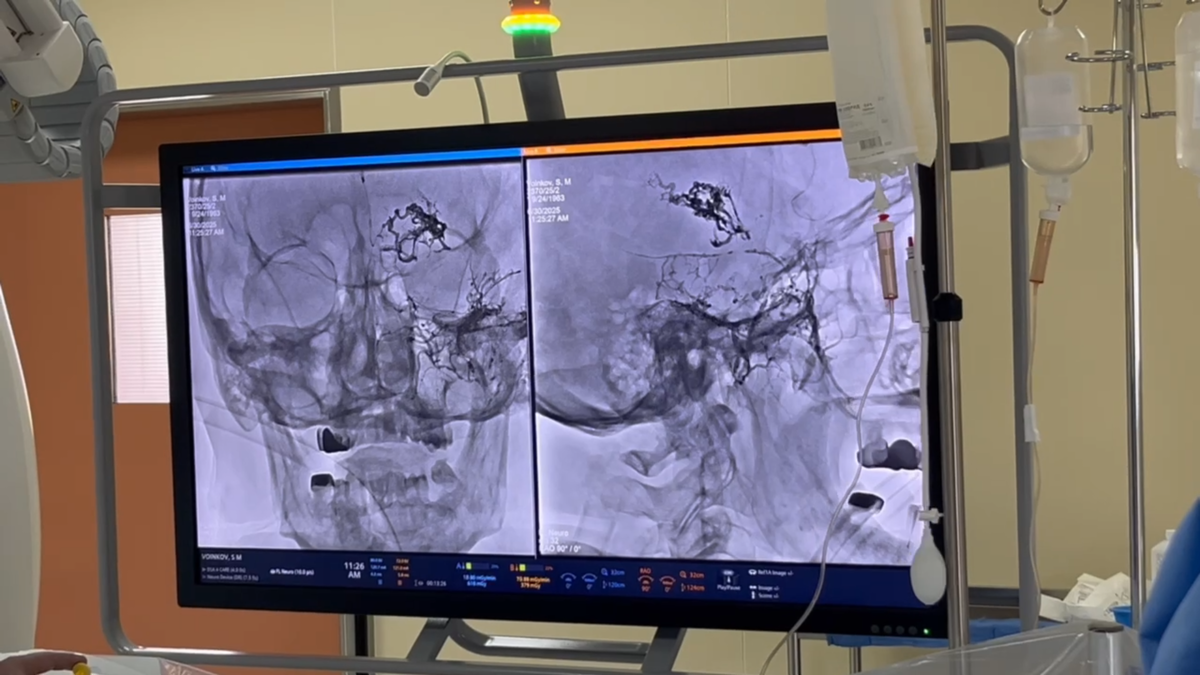

В Федеральном центре нейрохирургии (ФЦН) Тюмени произошло событие, которое перевернёт представление о возможностях медицины в России. Здесь открылась уникальная операционная с биплановым ангиографом последнего поколения – это первый в стране аппарат такого уровня для нейрохирургии.

Как рассказали врачи в эксклюзивном интервью программе "Вечерний хэштег" телеканала "Тюменское время", это не просто новое оборудование – это революция в лечении сложнейших заболеваний мозга. Теперь врачи могут проводить операции, которые раньше были невозможны, а пациенты получают шанс на спасение даже в самых тяжёлых случаях.

- Две плоскости сканирования одновременно, КT и МРТ одномоментно

- 3D-изображение в реальном времени – хирург видит мозг пациента в объёме прямо во время операции.

- Искусственный интеллект – прогнозирует результат вмешательства, помогает выбрать инструменты и снижает риски.

- Минимальная доза облучения и контраста – безопасность для пациента выше, чем когда-либо.

- Операции в разы быстрее – вместо полутора часов всего 20-30 минут!

"Мы много лет мечтали о таком аппарате. Это настоящий прорыв! Теперь мы можем лечить пациентов, которых раньше считали безнадёжными. Благодаря двухплоскостному сканированию и 3D-визуализации мы видим мозг так, как никогда раньше. Это как GPS для сосудов – мы точно знаем, куда идти".

"Теперь мы можем заранее "проиграть" операцию на виртуальной модели. Искусственный интеллект подсказывает, какие инструменты выбрать и как избежать осложнений. А главное – пациент получает минимальную лучевую нагрузку, потому что аппарат делает всё за один проход".

Список заболеваний, которые теперь можно лечить с невероятной точностью, впечатляет:

- Аневризмы глубоких артерий

- Артериовенозные мальформации

- Опухоли головного и спинного мозга

- Сосудистые патологии

Операции проводятся через крошечный прокол в артерии – никаких больших разрезов. Микроинструменты толщиной с волос (1,5–2 метра в длину!) доставляются к очагу болезни с ювелирной точностью.